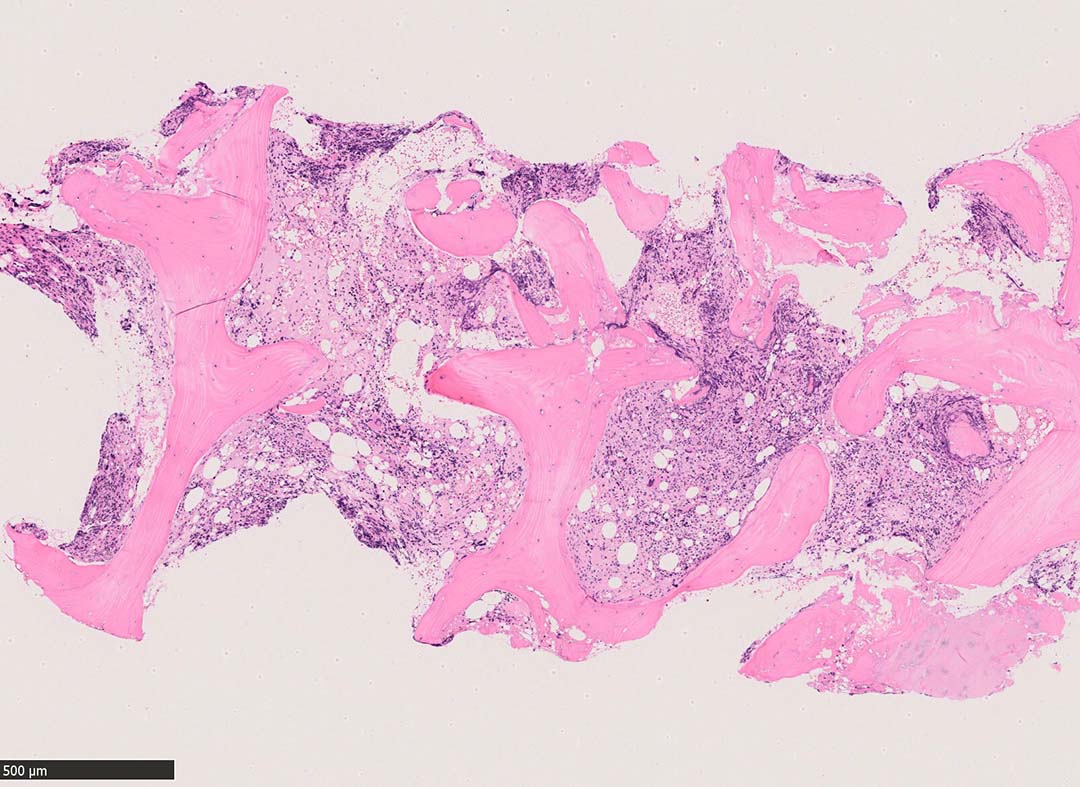

骨髄組織所見 bone marrow biopsy total 6mm in length

Case02; Meylofibrosis, overt fibrosis

77year-old female. 40歳時polycythemia veraと診断されていた.

[注] この症例は詳細は不明であるが, 過去にPVと診断されているため, PVに伴う二次性のmyelofibrosisの診断になる.

黒染する弾性線維の増生のほか, 赤く染まる膠原線維の増生が確認される. MF-2 fibrosis. 鍍銀染色の核染色をすると膠原線維の赤染がわからなくなるので行わない.